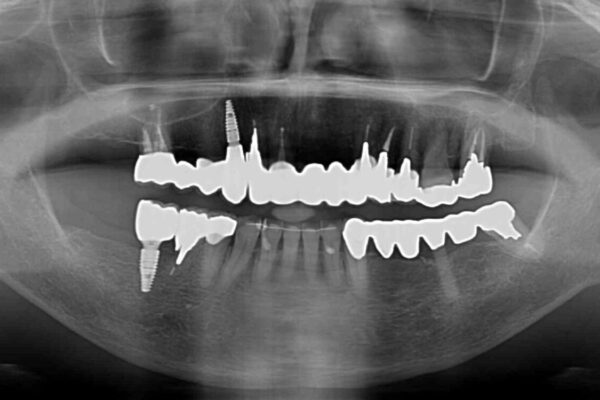

上顎犬歯や下顎大臼歯は、必要なところはインプラントを埋入することとしました。

クラウンが不適合であったり、根管治療の必要なほどの痛みのある歯であったり、見た目の気になる前歯などをオールセラミッククラウンに補綴治療を行うこととしました。

処置を予定していた歯を仮歯に変えた時点で、下顎前歯の部分矯正を行うかどうかを尋ねたところ、折角なので行いたいと言うことでしたので、矯正治療を行うこととしました。

インプラント埋入や根管治療治療など、治癒に一定の期間を要する処置の合間に矯正治療を行うことで、効率的に治療を進めて行くことができました。